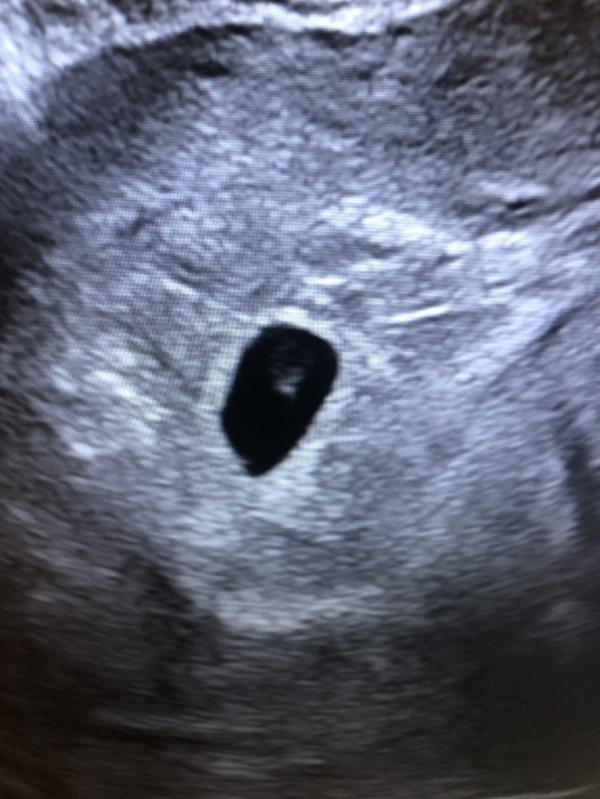

Отсутсвие месячных и аппетита все же беременность.

Узи подтвердило 5 недель и отправили ещё 2 недели гулять. Ждём сердцебиения.